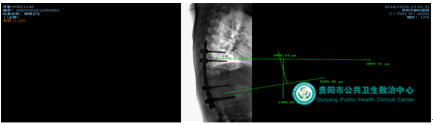

病例1:病人是由省級醫(yī)院轉(zhuǎn)診的腰椎結(jié)核患者,腰痛明顯,行走時(shí)感下肢麻木;腰4、5椎體破壞,尤其腰4椎體僅剩0.3cm厚,單純填塞骨頭支撐力度不夠,手術(shù)時(shí)采用鈦籠植骨支撐,但后路脊柱手術(shù)開窗小,放置鈦籠難度大,經(jīng)過精心設(shè)計(jì)成功從后路完成鈦籠放置。

術(shù)后